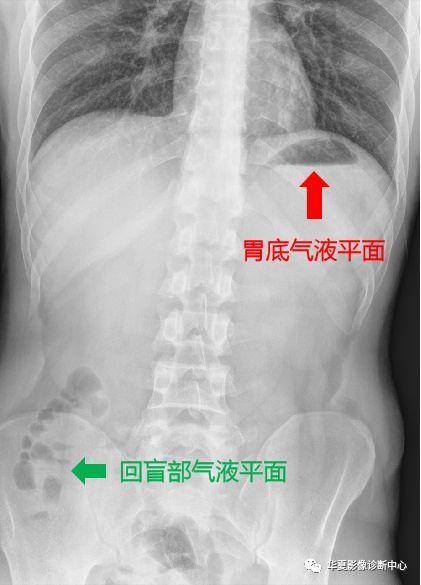

十二指肠球部(灯泡样),回肠末段及结肠胃底腹部常见的正常气-液平面

腹部气液平面x线图片